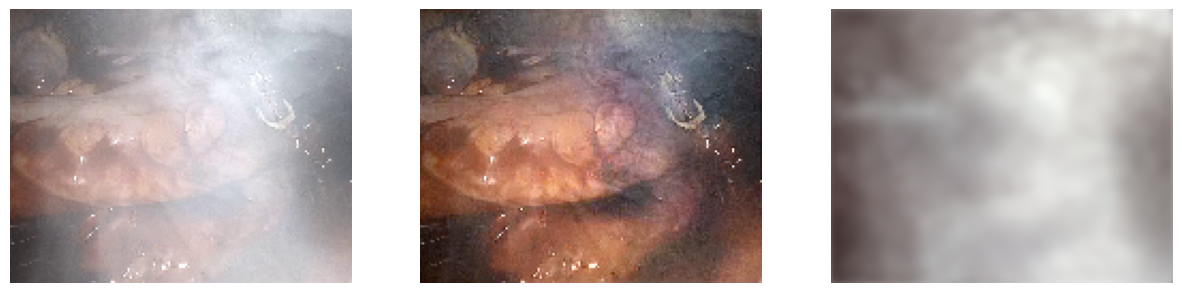

Desmoking Results

Our transformer-based model removes surgical smoke in real time, recovering scene content behind dense smoke with minimal color distortion.

Heart — Ours (Synthetic Only)

Heart — Ours (Fine-tuned)

Qualitative Comparisons

Qualitative comparisons across representative scenes (liver and stomach). Our method recovers scene content behind dense smoke with minimal color distortion and fewer artifacts compared to existing dehazing and desmoking approaches.